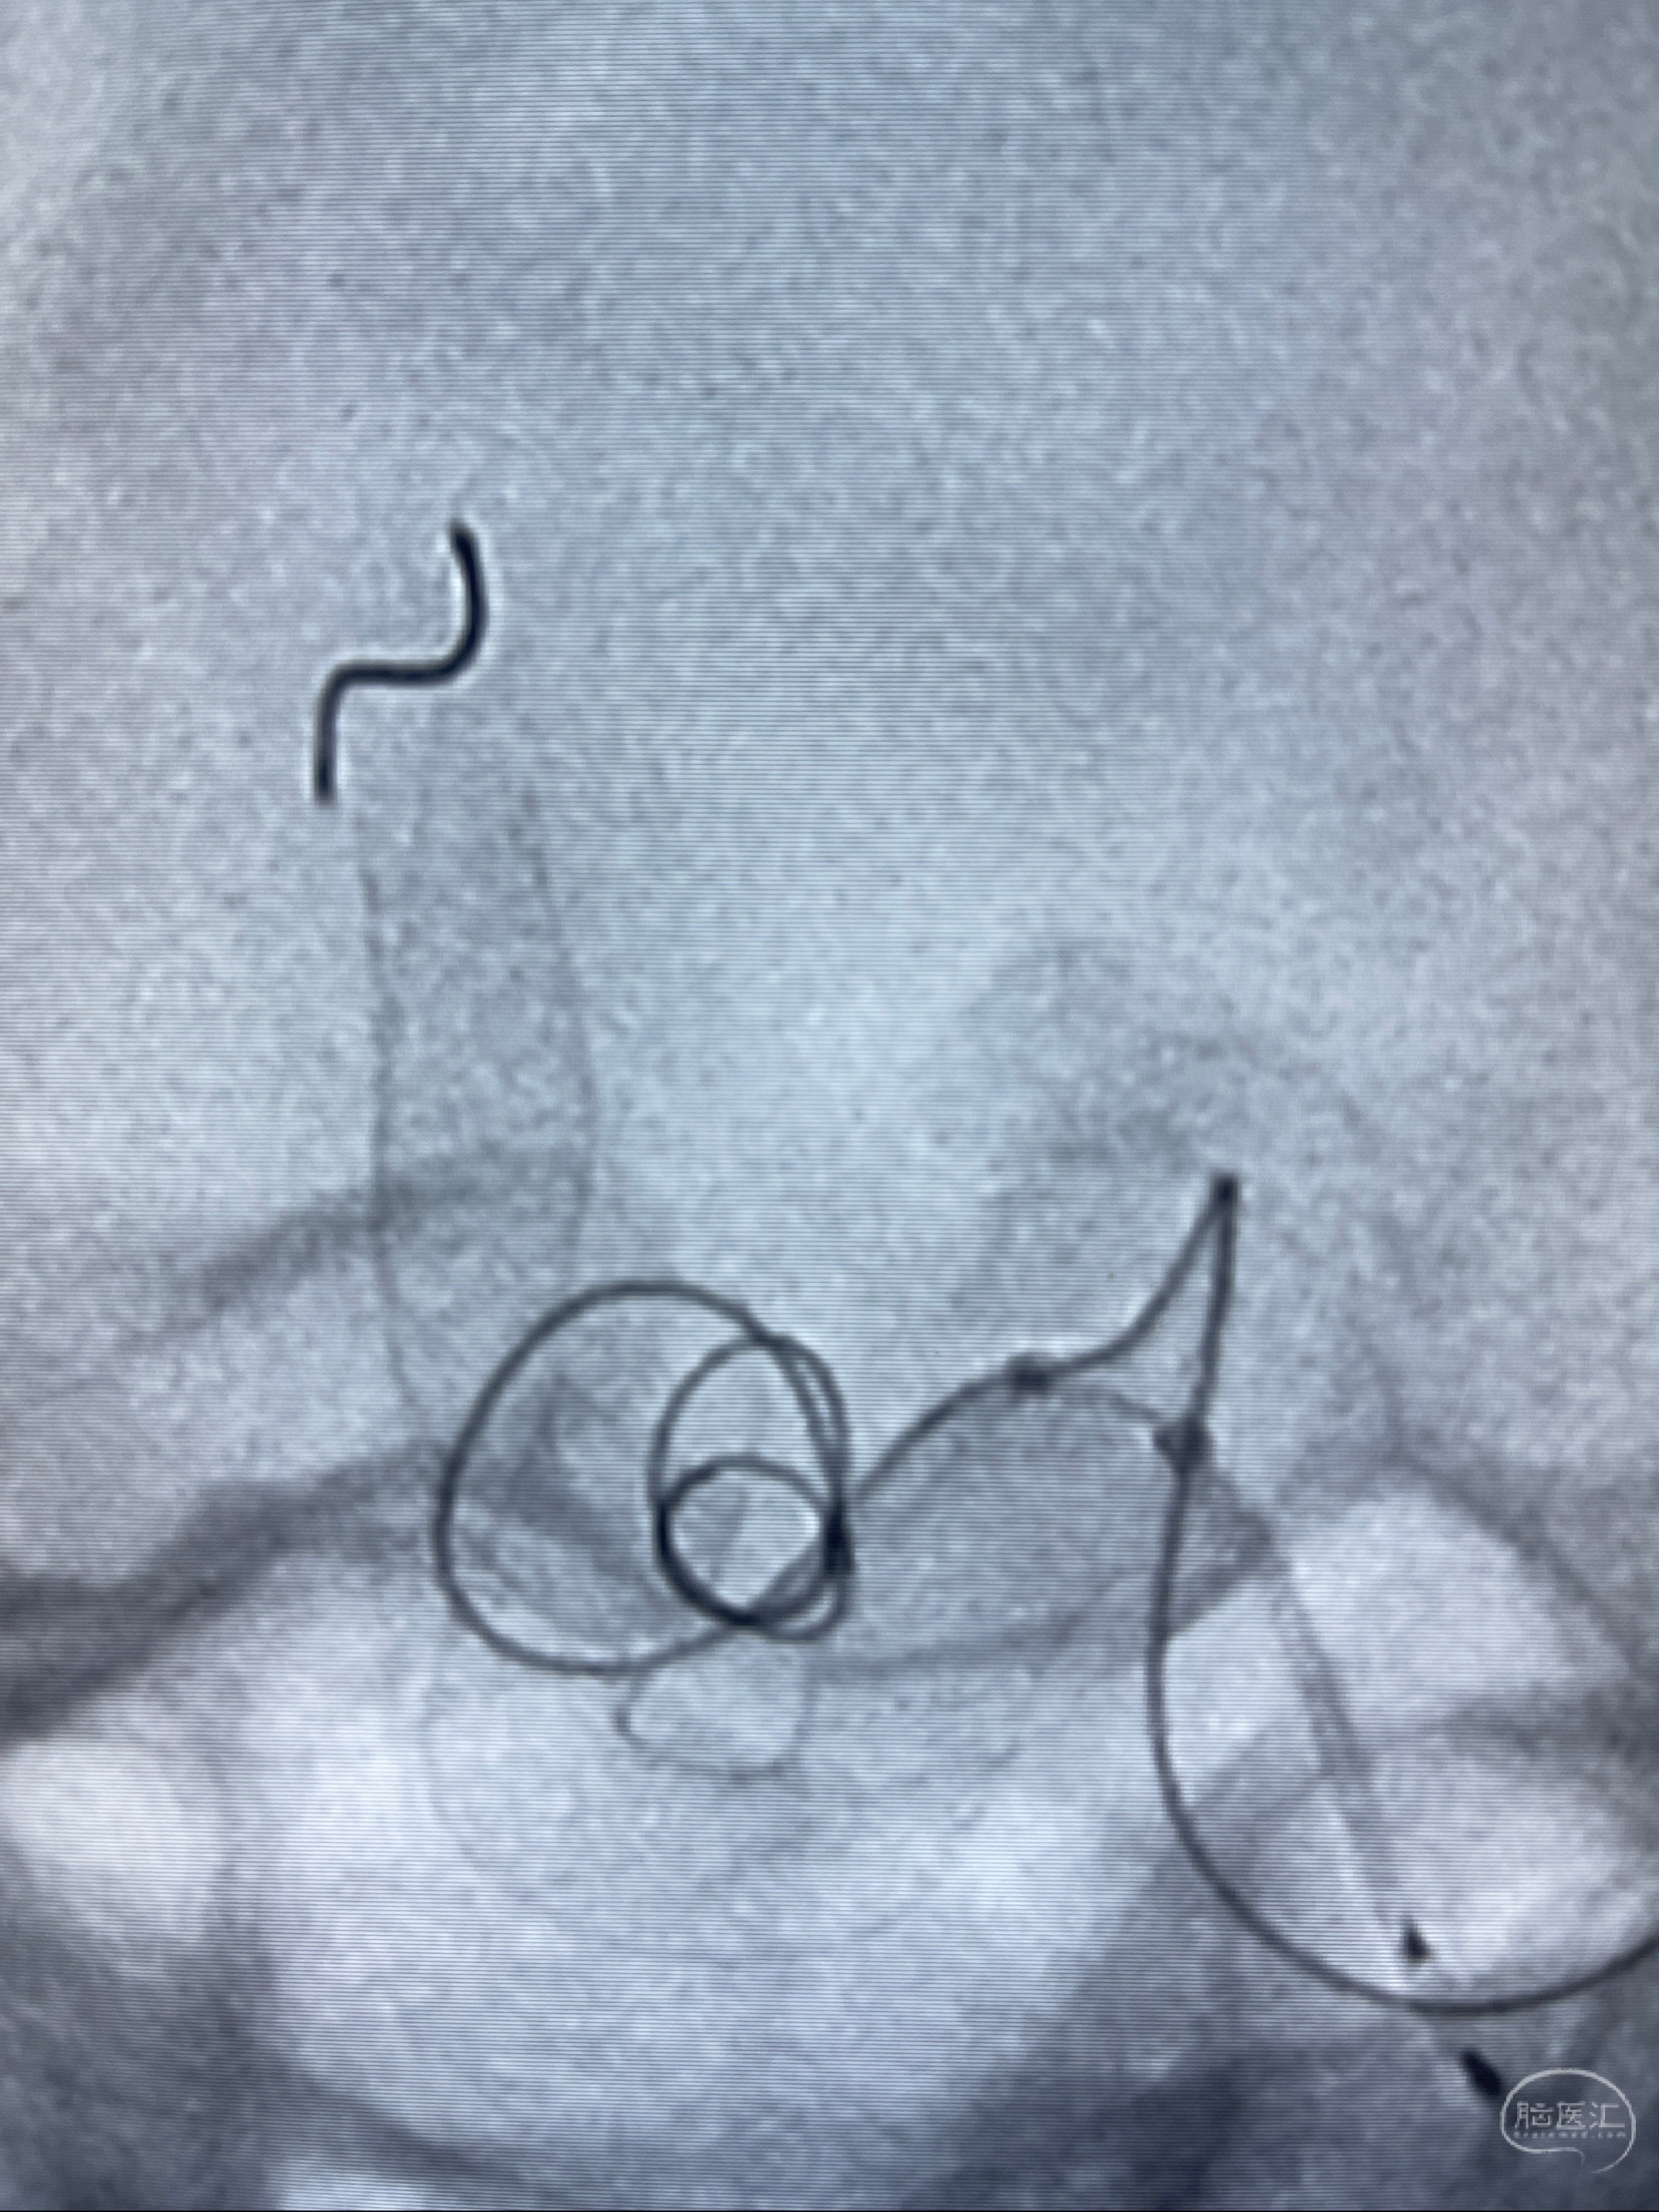

2023-07-27全脑血管造影:双侧颈内动脉眼动脉段动脉瘤,右侧较大

2023-08-01全麻下行双侧颈眼动脉瘤支架辅助栓塞

- pipeling4.5-20mm

- pipeline 4.0-20mm